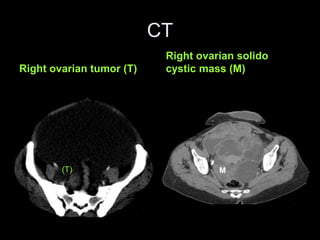

Right ovarian tumor (T)

Right ovarian solido

cystic mass (M)

(T) M

CT Right ovarian tumor(T) Right ovarian solido cystic mass (M) (T) M